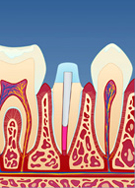

Dersom rotfyllingen vurderes og finnes tett og av god kvalitet, fjernes en del av rotfyllingsmassen for å gjøre plass til stiften (fig. II). Deretter kan stiften festes med en egnet sement (fig. III). Rundt stiften bygger man så opp en masse (konus) som slipes og formes til (fig. IV). Nå kan man ta avtrykk av den beslipte tannen, sende dette til en tanntekniker og få den ferdige kronen tilbake klar for sementering (fig. V og VI). Hele prosessen tar vanligvis 1 til 2 uker.

| figur II | | figur III | | figur IV | | figur V | | figur VI |